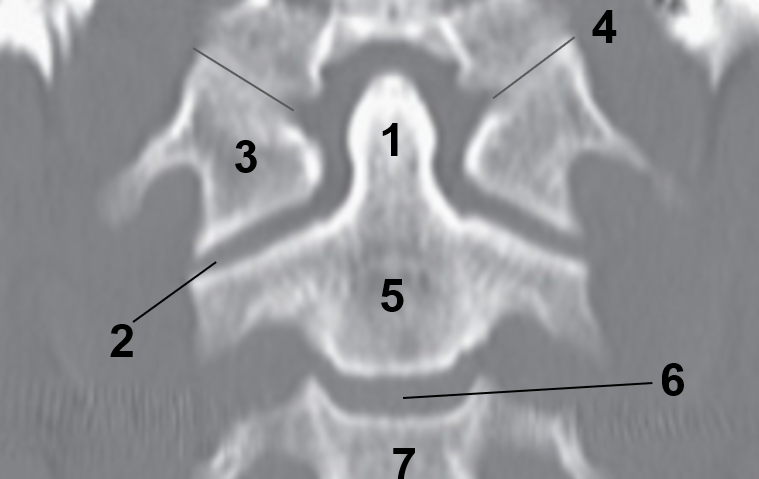

1?

Nasal Bone

2?

Maxillary Sinus

3?

External Acoustic Meatus

4?

Pons

5?

Cerebellum

6?

Mastoid Air Cells

7?

Mandibular Condyles

8?

Sphenoid Bone

9?

Maxillary Bone